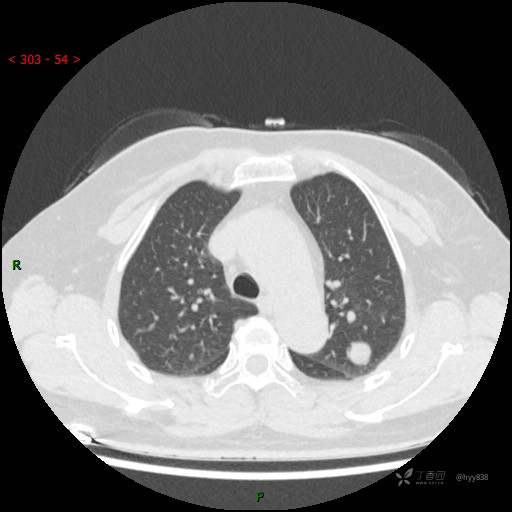

孤立肺结节,还为遇到过这么“圆”的,是否如你心中所想---结果公布~

患者性别:女

患者年龄:55岁

主诉:背部疼痛不适7月余

简要病史:患者7月前无明显诱因出现背部疼痛不适、呈胀痛,2022-12-12至当地人民医院行胸部CT检查示:左上肺占位,建议增强检查。患者未行进一步检查及治疗,患者现背部疼痛进行性加重,无咳嗽、咳痰,无心慌、胸闷、无胸痛、反酸、发热等,为求进一步诊治,来我院就诊,门诊以“肺肿物”收入我科。 患者病程中,精神食欲可,二便正常,体力体重较前变化不明显。

辅助检查:CT

临床诊断:肺肿物

讨论:结节性质?

胸部CT平扫